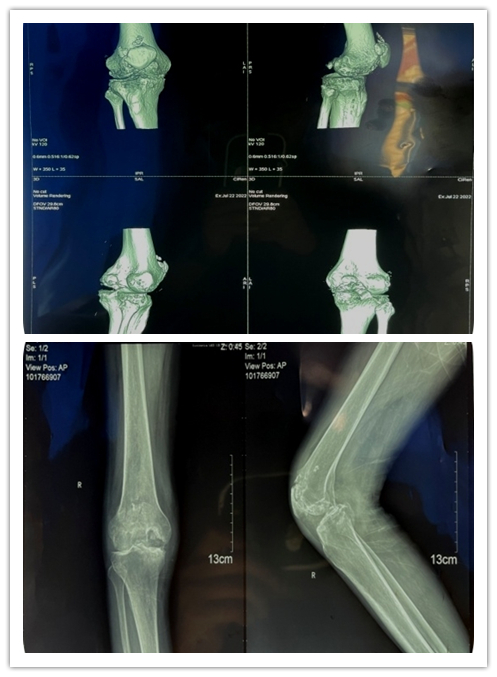

入院后检查后发现,患者营养不良并伴有低蛋白血症,右膝畸形严重,右侧膝关节内翻(内翻15度),是我们常说的“O形腿”,右侧膝关节周围压痛明显,膝关节活动范围10-90°。术前X光片提示右侧膝关节内翻畸形,股骨远端重度缺损。经多学科讨论及评估,医疗团队为患者行右侧人工全膝关节置换手术,从而缓解膝关节疼痛,改善膝关节功能,提高生活质量。

结合患者的情况,为保证患者获得最佳的治疗效果,术前完善CT三维重建,明确骨缺损部位,提前制定多套术中应对骨缺损处理的方案,并在术前准备了最小型号的假体,股骨侧垫块、延长杆及增强型内衬垫片。